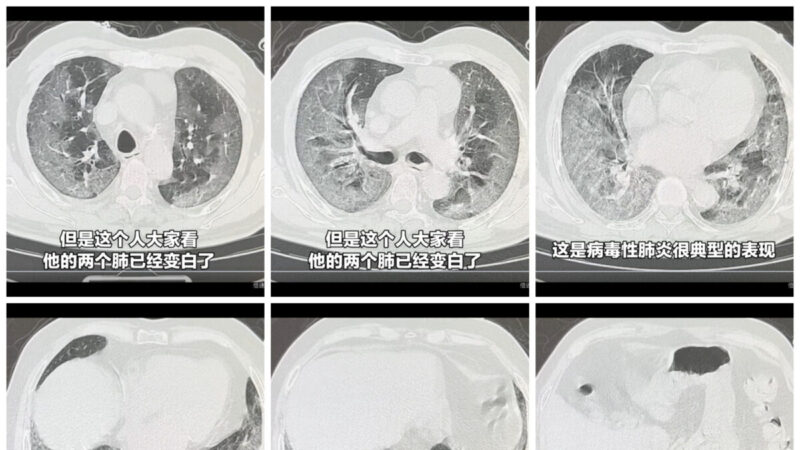

山西中醫李醫師:「斷斷續續也挺多,也挺嚴重,都是新冠,以前那種症狀,不精神,也有的是新的症狀,上吐下瀉,報的什麼諾如,(官方)起的各種名字都是新冠的變種,今年的白肺也死了很多人,年輕的還有十幾歲的孩子嘛,現在中國的醫院都是人滿為患。」

福建廈門市民李先生:「很多人都死了,都打苗(疫苗)引起的,打完體質變得沒有力量,一感冒就緩不過來,一般都是白肺、心臟問題。年紀還很輕,糖尿病、高血壓都出來了,還有腎衰竭的,我所在的生活區,好幾萬人申請醫療救助和司法認證,行政命令下壓,就是到了醫院也沒人敢說是打苗引起的。」